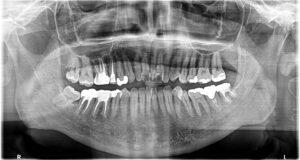

2年後、だいぶ骨ができてきました。

根の先の黒い影がだいぶ小さくなってきてます。